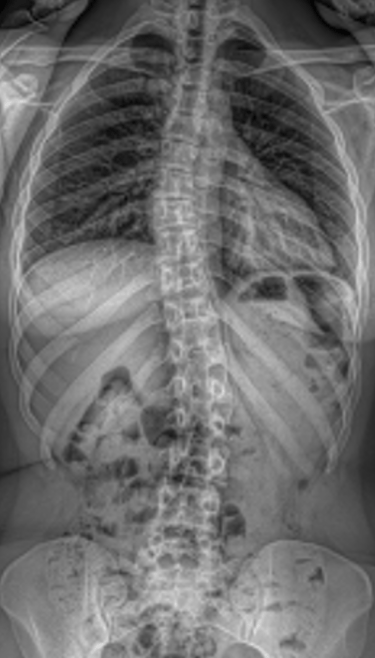

Scoliosis is a condition in which the spine curves sideways rather than growing in a straight line. It most often develops during childhood or adolescence, particularly during growth spurts, but it can also be present in adults. Many people with scoliosis experience no pain or noticeable symptoms, while others may notice pain, uneven shoulders or hips, a visible curve in the back, or clothing that fits unevenly.

Diagnosis is usually made through a physical examination and confirmed with X-rays to measure the spinal curve. Treatment depends on the curve’s size and the patient’s age, ranging from regular monitoring in mild cases to bracing, exercise-based therapy, or surgery for more severe scoliosis. With appropriate care, most patients are able to remain active and live healthy lives.